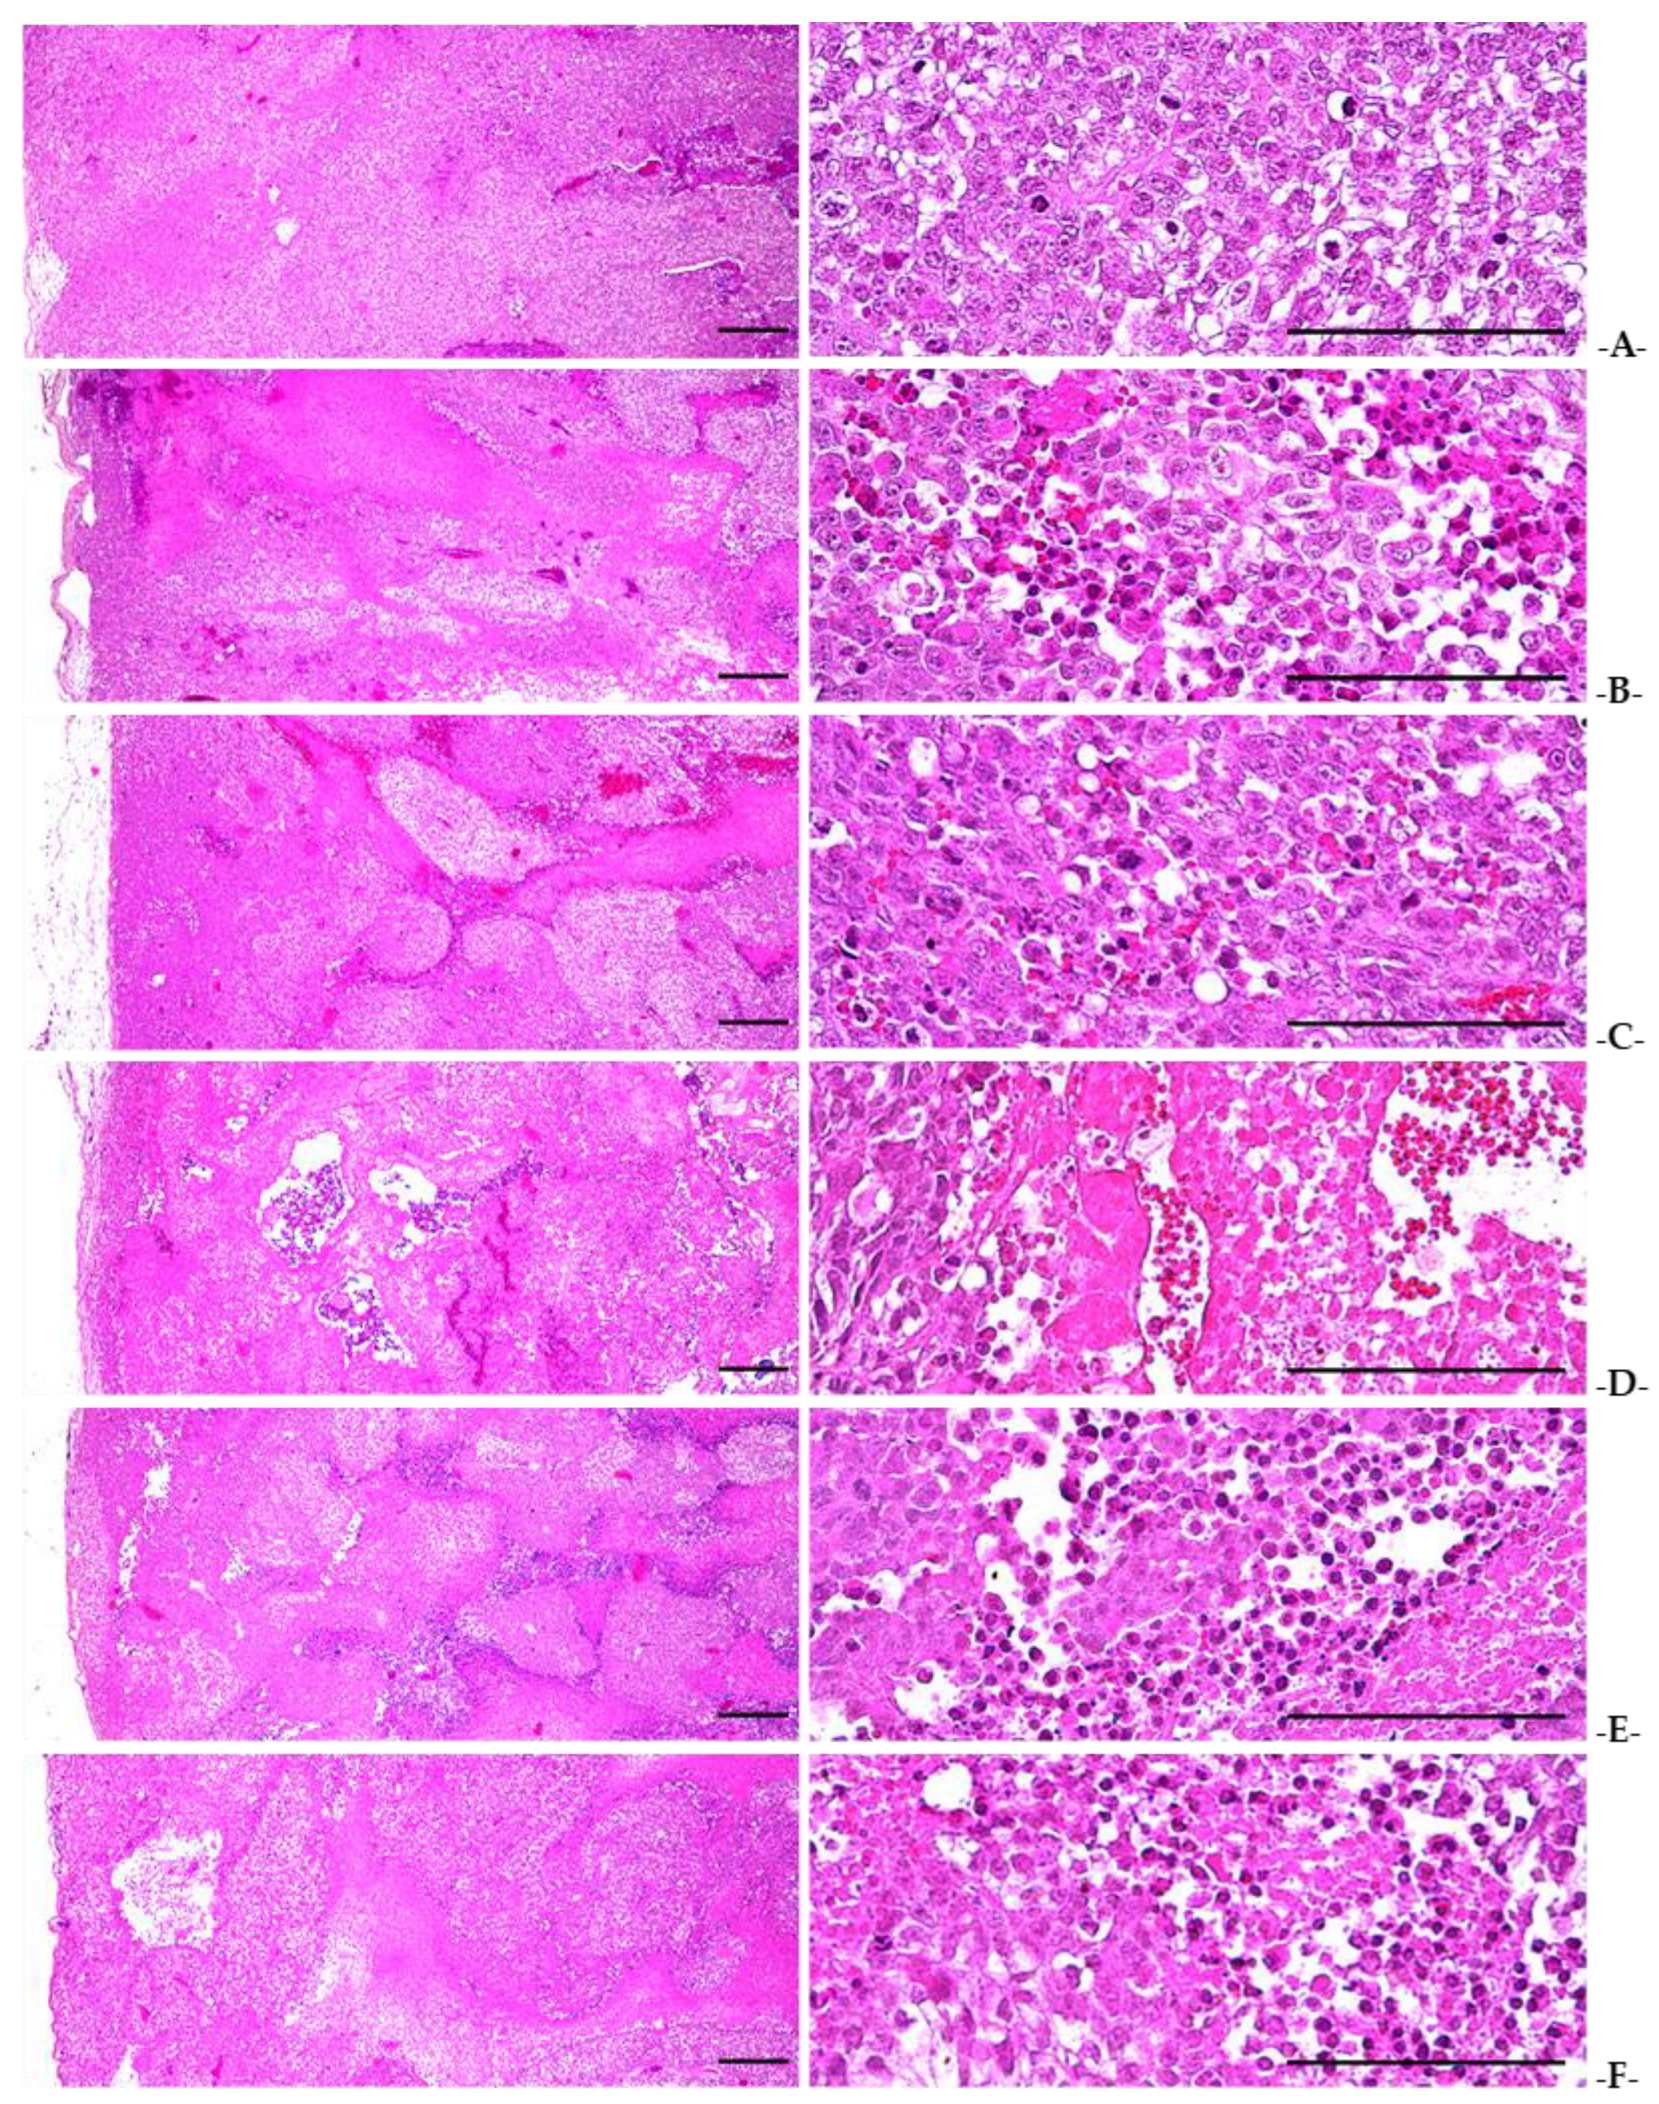

In the tumor transplantation control group, the tumor was densely composed of relatively well-differentiated NCI-H520 lung cancer cells. Cytoplasmic eosinophilic increase and nuclear enrichment due to apoptosis were confirmed in some cells, and mitosis was also frequently observed. In contrast, a significant increase (p < 0.01) in the number of apoptotic cells was confirmed in the gefitinib- and sasam-Kyeongokgo-alone groups and in all the sasam-Kyeongokgo and gefitinib combination groups compared with the tumor transplantation control group. The proportion of NCI-H520 cells was also significantly reduced (p < 0.01). In particular, a significant decrease (p < 0.01) in the tumor cell volume and an increase in the number of apoptotic cells were observed in the sasam-Kyeongokgo and gefitinib combination groups in comparison with the gefitinib-alone group (Table 6, Figure 7). In addition, the sasam-Kyeongokgo and gefitinib combination administration groups, the gefitinib single administration group, the sasam-Kyeongokgo-alone group, and the sasam-Kyeongokgo 400 mg/kg single administration group showed a significant caspase-3 and PARP immune response (p < 0.01) in the tumor mass. An increase in the number of cells was confirmed in comparison with that observed in the tumor transplantation control group. In particular, a significant increase (p < 0.01 or p < 0.05) in the number of PARP- and caspase-3-immunoreactive cells was confirmed in the sasam-Kyeongokgo and gefitinib combined administration groups compared with the gefitinib-alone group (Table 6, Figure 8 and Figure 9). In the sasam-Kyeongokgo-alone and all the sasam-Kyeongokgo-co-administered groups, the tumor masses showed a significant increase (p < 0.01) in the number of iNOS and TNF-α immunoreactive cells and a decrease in the number of COX-2 immunoreactive cells in comparison with the transplant control group. In particular, the sasam-Kyeongokgo and gefitinib combination administration groups showed a significant increase (p < 0.01 or p < 0.05) in the number of iNOS and TNF-α immunoreactive cells and a decrease in the number of COX-2 immune-reactive cells in comparison with the gefitinib-alone administration group. On the other hand, a significant decrease (p < 0.01) in the number of COX-2 immunoreactive cells was confirmed in the gefitinib-alone group in comparison with the tumor transplantation control group. However, there were no significant changes in the iNOS- and TNF-α immune response cells (Table 6, Figure 10, Figure 11 and Figure 12).

Figure 7.

Representative histological profiles of the tumor masses taken from NCI-H520 tumor cell xenograft mice. (A) = Tumor-bearing control; (B) = 120 mg/kg-gefitinib-single-treated rodents; (C) = 400 mg/kg-SKOG-single-treated rodents; (D) = gefitinib 120 mg/kg and SKOG 400 mg/kg; (E) = gefitinib 120 mg/kg and SKOG 200 mg/kg; (F) = gefitinib 120 mg/kg and SKOG 100 mg/kg. AR = Adenophorae Radix; KOG = Kyeongokgo; SKOG = sasam-Kyeongokgo. All Hematoxylin-Eosin-stained. Scale bars = 100 μm.